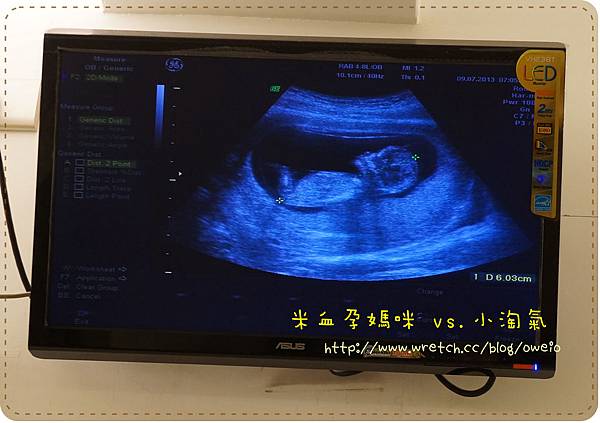

做完超音波一切完美之後就詢問院長有關於唐氏症篩檢這玩意,除了透過羊膜穿刺還有哪些資訊

其實網路之發達都可以查得到,只是想要更明白我所有疑問的兩者有什麼差別囉!![]()

之前我所知道的是第一孕期唐氏症篩檢,適合11W~13W+6d

主要是做母體抽血及透過超音波照胎兒的頸部透明帶![]()

然而,並不是每家醫院都可以做這項檢查,而台中市唯一也只有中國醫藥學院是合格認證的![]()

所以老娘我也早就預約好去中國醫給合格的醫生做這項檢查,而中國醫的自費價格是NT$2,700

言歸正傳,另一個就是四指標母血唐氏症篩檢,適合15W~20W

廢話不多說~因為字數太多又要被斷文章

直接給大家看個圖片比較清楚